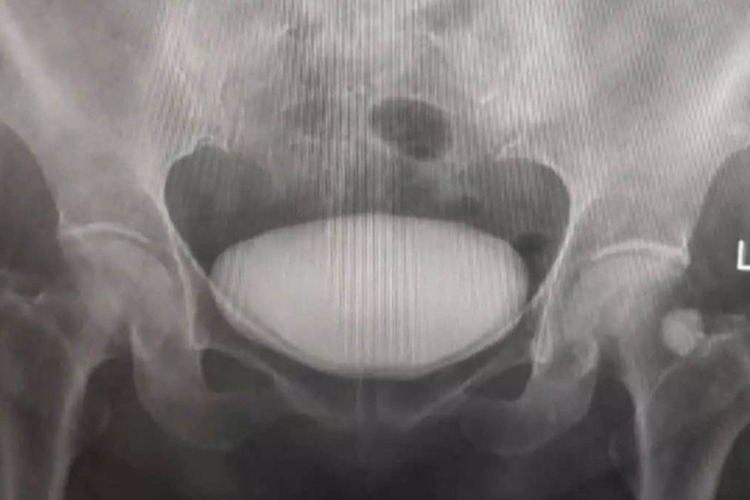

膀胱膨出属于前盆腔脏器膨出,是指膀胱向阴道前壁的膨出。多见于中老年妇女、多产妇。

根据阴道前壁脱垂情况,可将膀胱膨出分为三度,以评价疾病的严重程度。

根据阴道前壁脱垂情况可进行膀胱膨出的分度,以评价疾病的严重程度,可分为三度,轻者无症状,或有轻度下坠感、腰酸,重者可伴有排尿困难。

Ⅰ度

阴道前壁形成球状物,向下突出,达处女膜缘,但仍在阴道内。

Ⅱ度

阴道壁展平或消失.部分阴道前壁突出于阴道外口。

Ⅲ度

阴道前壁全部突出于阴道外口。